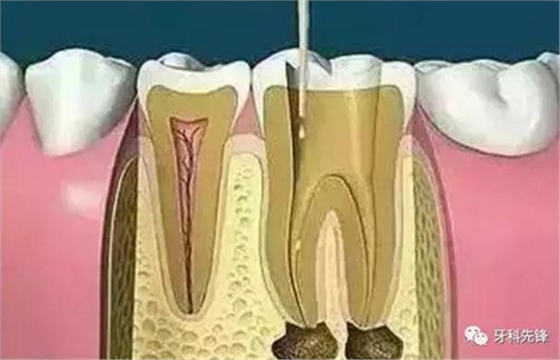

7、根管打樁

因牙體缺損過多,導(dǎo)致牙的強(qiáng)度(承受力量的性能)大幅度下降,不能很好地承受咀嚼力量。打樁的目的是增加牙根及牙冠的強(qiáng)度,增加患牙的穩(wěn)固。